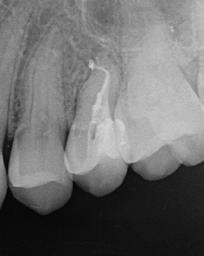

Az MB2 csatornát befecskendezéses technika alkalmazásával egy műgyanta alapú sealerrel töltöttem fel, míg a többi csatornát (MB, DB, P) ugyanezen sealerrel, de meleg guttapercha felhasználásával (continuous wave) töltöttem fel (9. ábra) . A perforációt ezt követően MTA-val (mineral trioxide aggregate) zártam (10. ábra) és kompozittal fedtem (11. ábra) . Több, excentrikus irányból készült periapikális röntgenfelvétel is készült. Ezeken egy további a mesialis gyökér apikális részén végigfutó sealer csíkot és a mesialis gyökér csúcsánál látható sealer puffot sikerült megfigyelni (12–13. ábra)

A mesialis gyökér megfelelő endodonciai ellátásának ellen őrzése céljából a pácienst egy kontroll CBCT-felvételre irányítottuk. A felvételen látható volt, hogy az MB2 csatornát teljes terjedelmében ki tudtuk tölteni a sealerrel, továbbá, hogy az apikális harmadban az MB1 és MB2 csatornák között egy keskeny összeköttetés található, valamint hogy az MB1 és MB2 gyökércsatorna különálló végződéssel rendelkezik (14. ábra) . A fogat kompozitfelépítéssel láttuk el, majd visszairányítottuk a beküldő orvosához. Csücsökborítást biztosító indirekt restaurátum készítését javasoltuk, illetve 6 hónap múlva kontrollvizsgálat céljából visszarendeltük magunkhoz. A 6 hónapos kontroll során készített CBCT-felvételen a gyökércsúcsok körül nem voltak gyulladásra utaló jelek. A fog teljesen panaszmentes volt és a Schneider membrán megvastagodását sem észleltük (15. a–b ábra.).